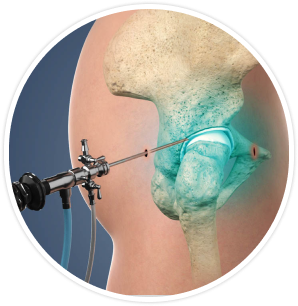

Hip joint arthroscopy is a minimally invasive surgical procedure that involves the use of a small camera and instruments to diagnose and treat various hip joint conditions. It is commonly used to address issues such as hip impingement, labral tears, cartilage damage, and loose bodies within the joint.

Small incisions are made around the hip joint to allow the arthroscope and other surgical instruments to be inserted without causing excessive trauma to the surrounding tissues.

Visualisation is achieved by inserting the arthroscope, a small camera attached to a flexible tube, into the hip joint to provide a clear view of the internal structures.

Insertion of the arthroscope into the hip joint allows the surgeon to examine the cartilage, ligaments, and other tissues for any abnormalities that may require intervention.

Tissue repair or removal may be necessary during hip arthroscopy to address issues such as labral tears, loose bodies, or inflamed synovium that can cause pain and limited mobility.

Bone reshaping/trimming may be performed to correct any abnormalities in the shape of the hip joint, such as removing excess bone or reshaping the socket to improve stability and range of motion.